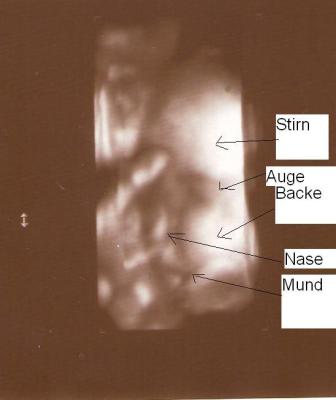

Bei der Ultraschalluntersuchung jedoch wollte es dann nicht mehr. Es war absolut schwierig ein Bild zu schießen, denn der/die Kleine hielt sich die ganze Zeit den Arm vors Gesicht. So kann man also nur mit Müh und Not auf dem Foto ein Auge, die Wange und den Arm erkennen.